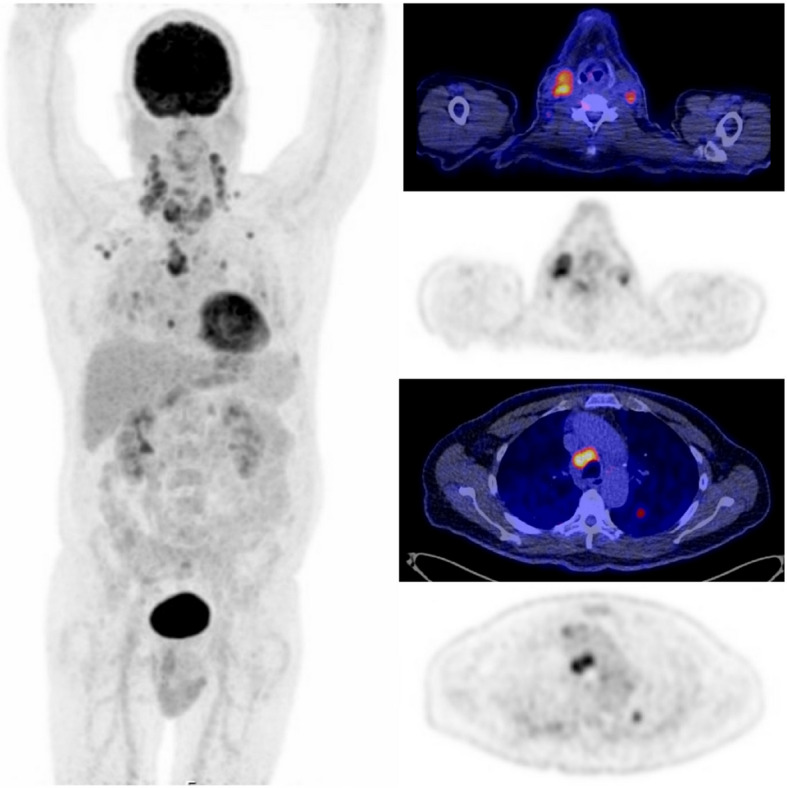

Results: A total of 175 MTC patients were included (91 females and 57 hereditary MTCs). Median age at presentation was 52 years (IQR 38 - 62). Initial treatment included a total thyroidectomy, CND and LND in 155 (89%), 140 (80%) and 59 (33%) patients. Preoperative imaging of the neck included ultrasound (91, 52%), MRI (33, 19%) and CT (31, 18%). PET/CT imaging was performed in 56 (32%) patients (35 18F-FDG PET/CTs and 33 18F-DOPA PET/CTs). Sensitivity for LNM in the central compartment was 72%, 39%, 6%, 42% and 93% for 18F-FDG PET/CT, 18F-DOPA PET/CT, ultrasound, MRI and CT, respectively. Respective specificity rates were 80%, 100%, 100%, 71% and 100%. Sensitivity rates for lateral neck LNM were 89%, 81%, 77%, 76% and 75%, for 18F-FDG PET/CT, 18F-DOPA PET/CT, ultrasound, MRI and CT, while specificity rates were 100%, 100%, 75%, 78% and 50%, respectively. Twenty-three patients had distant metastases on imaging. In total, 14 18F-FDG PET/CTs and 9 18F-DOPA PET/CTs were made in these 23 patients (both in six patients). All but one PET/CT showed distant metastases.

Conclusions: PET/CT is a powerful tool to detect locoregional LNM and can particularly help identify cases where LNDs are required, avoiding reoperation later on. For accurate staging of the central neck, PET may be combined with diagnostic CT. Finally, PET/CT's ability to detect distant metastases may support de-escalation of a surgical intervention when cure is unlikely.